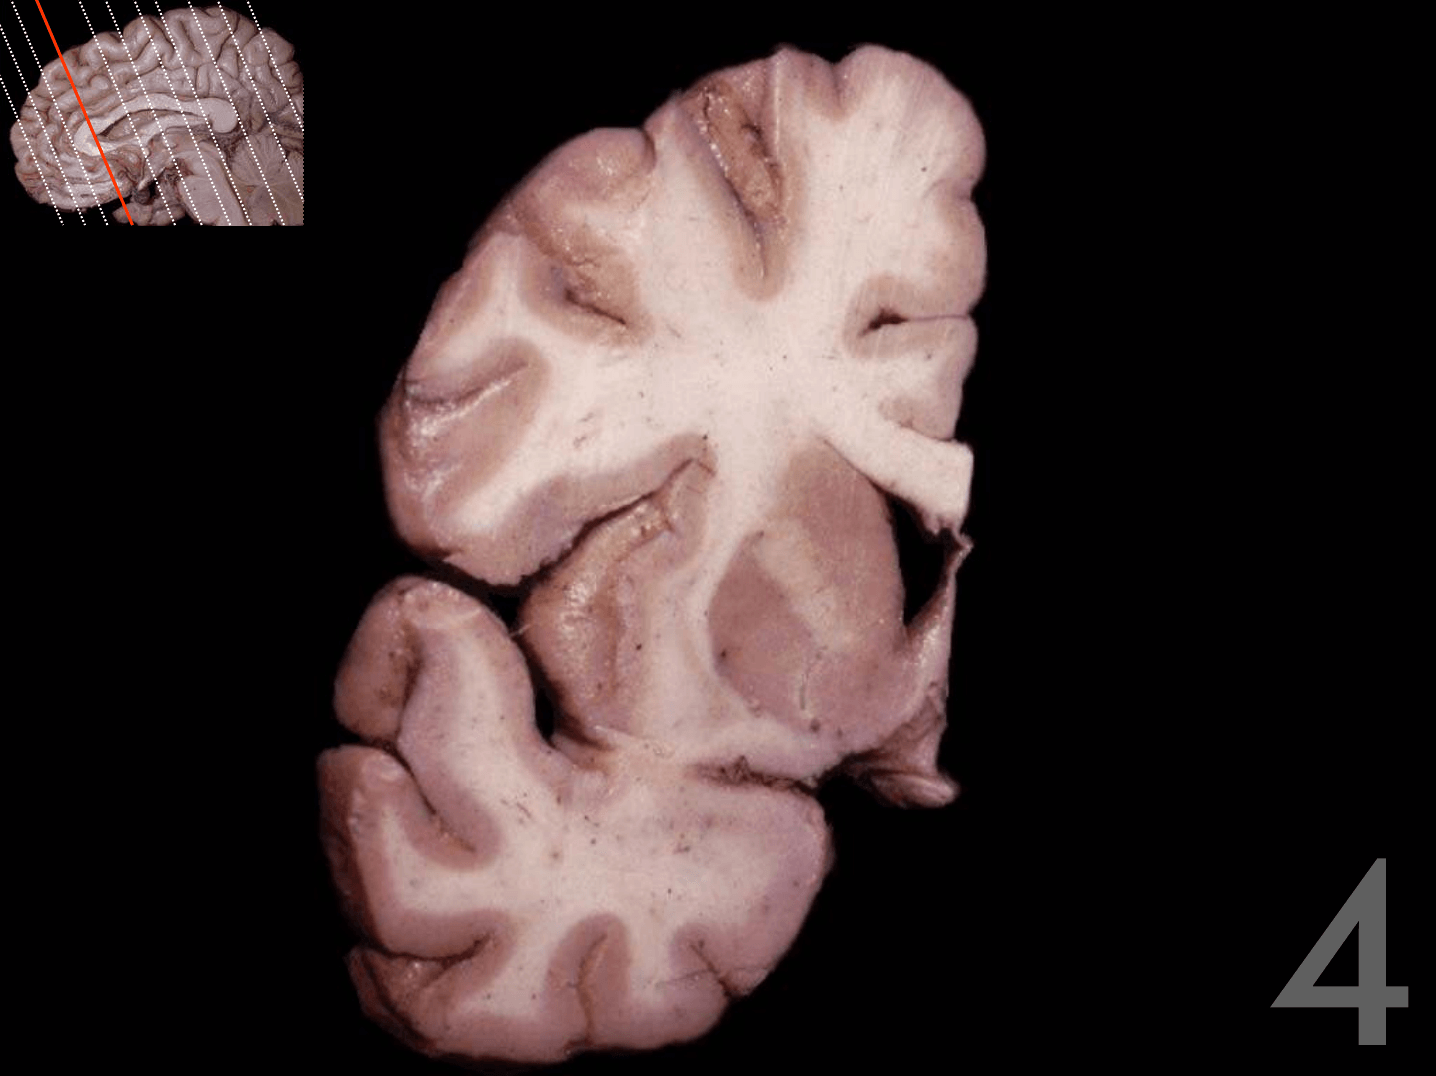

Tronco del cuerpo calloso

Rodilla del cuerpo calloso

Columna del fórnix

Comisura anterior

Foramen interventricular

Infundíbulo

Habénula

Pico del cuerpo calloso

Acueducto del mesencéfalo

Estría medular del tálamo

Adhesión intertalámica

Lámina terminal

Quiasma óptico

Tubérculo mamilar

Comisura posterior

Glándula pineal

Rodete del cuerpo calloso

Calota mesencefálica

Túber cinereum